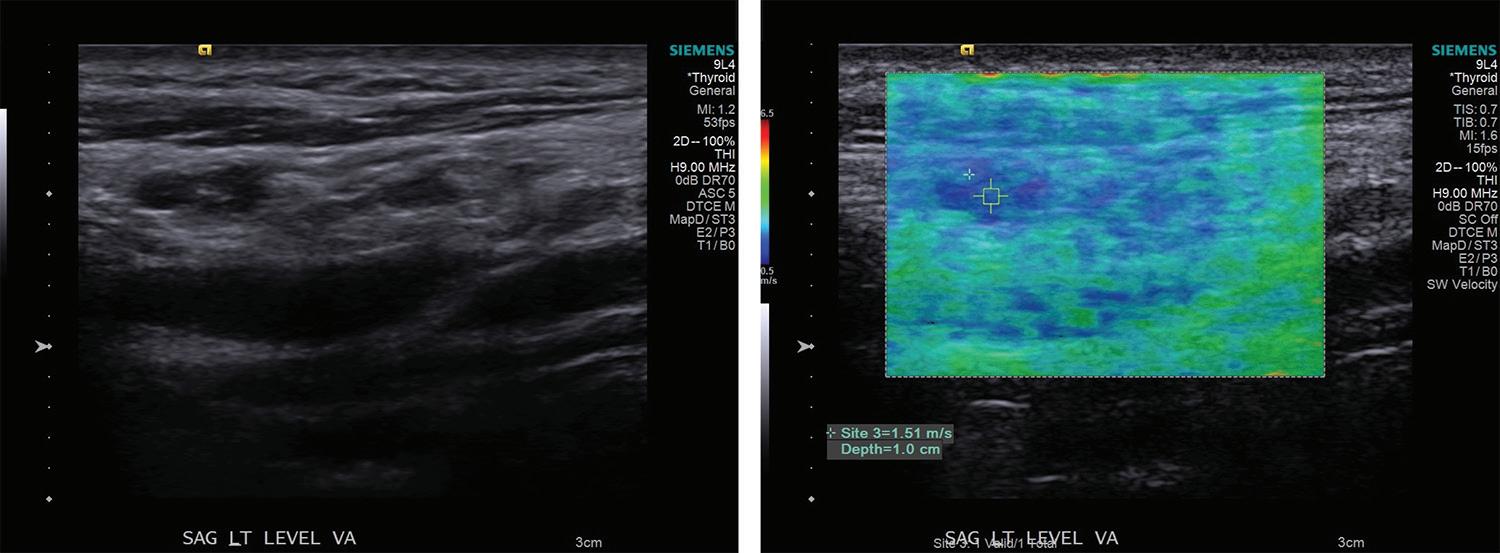

Volume 97, Number 1-2 www.entjournal.com 31 ORIGINAL ARTICLE

Additionally, diagnosis of lymph node invasion on presentation also serves as an important prognostic indicator for locoregional recurrence after the initial surgery.10,11

Approximately 30% of patients may develop recurrence following resection of primary disease, which is often associated with increased morbidity and mortality.12-14 PTC most often recurs or persists in cervical lymph nodes; therefore post-thyroidectomy surveillance with sonography of the neck and measurement of serum thyrogobulin level is required in the first 6 to 15 months and at regular intervals thereafter. The frequency with which patients are evaluated depends on serum thyroglobulin level and other risk factors.9

In evaluating recurrent disease, US findings have a reported sensitivity of 90%, specificity of 79%, and accuracy of 87.9%.8 The propensity of PTC for lymphatic spread and its effect on management of the disease underscores the need for accurate evaluation of cervical lymph nodes before and after thyroidectomy.

Elastography is a novel imaging modality that can be used clinically to assess elasticity of soft tissues. Elasticity is a parameter based on the strain or deformation of tissue in response to a physical force. Most malignancies reliably exhibit reduced elasticity and increased stiffness due to the nature of neoplastic growth, making this procedure a promising new development in the diagnosis of cancerous and metastatic foci.

The elastrography technique involves applying a force on the tissue and subsequently imaging the resultant deformation. This technique initially required the operator to physically push the transducer into the tissue to be examined, now termed quasi-static imaging. The unintended variable with

this technique was the differences in the degree of pressure applied by each observer. In efforts to increase objectivity and reproducibility, the acoustic radiation force impulse (ARFI) technique was developed, which involves emitting acoustic pulses inside tissue to generate micron-scale displacement.15

The distortion of tissues can be observed by ultrasonographic imaging, and areas of decreased strain can be recorded, creating a map of elasticity, known as an elastogram (figures 3 and 4). Additionally, whereas deformation can provide qualitative indications of tissue stiffness, measuring the speed of the shear wave, which is the speed with which the tissue wave travels perpendicularly from the pulse, can provide quantitative measurements of higher clinical value.16

Newer ARFI models can be used to measure shear wave velocity, which is inversely proportional to tissue elasticity, providing a means of numerical data collection.17 Supersonic shear imaging (SSI) or shear wave elastography (SWE) combines the technology of an applied ultrasonographic beam with ultrafast US imaging to create real-time, quantitative maps of tissue stiffness.18 Many newer models of US machines now have ARFI and/or SSI/SWE-based capabilities.

Review of literature